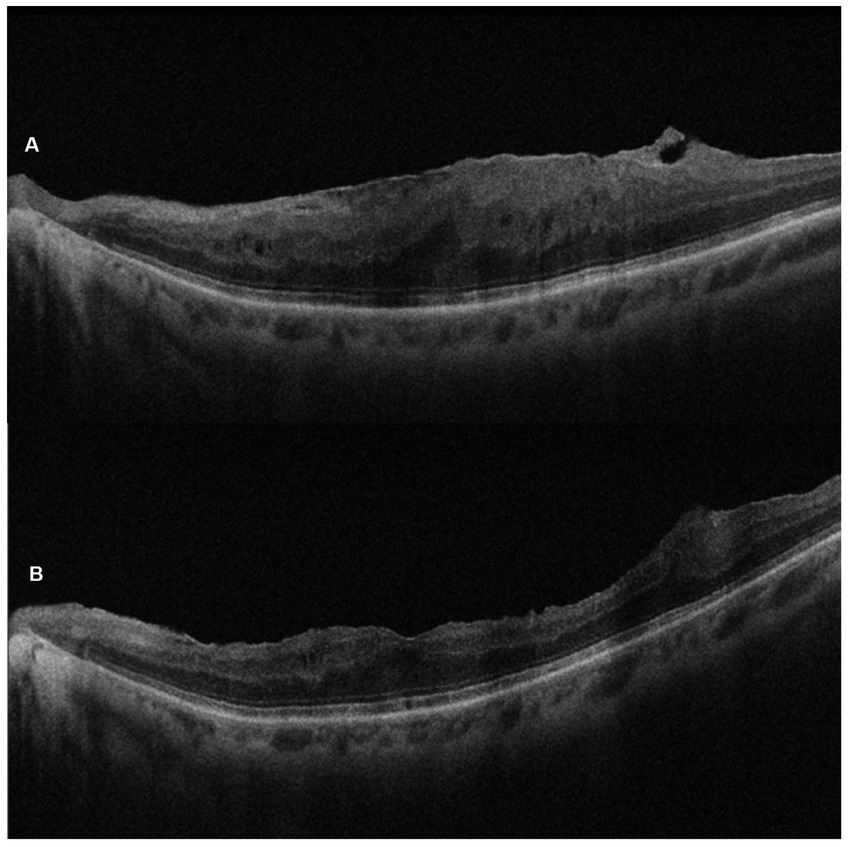

Figure 5

SD-OCT pre-operative (A) and 6-month post-ERM surgery (B) images of the left eye of a 67-year-old woman. Note the successful peeling and the morphological recovery of the foveal profile.